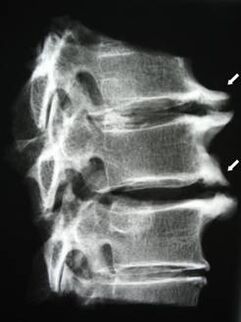

Nas fases iniciais, a osteocondrose detéctase mediante resonancia magnética. Máis tarde, a patoloxía pódese diagnosticar mediante radiografía. Nas radiografías da columna cervical nótanse unha redución da distancia entre as vértebras, cambios patolóxicos nas articulacións facetarias e osteofitose.

| Osteocondrose cervical | A aparición de cambios patolóxicos nun ou máis segmentos de movemento da columna vertebral. Mobilidade prexudicada da columna vertebral, desenvolvemento de síndromes de dor miofascial e beliscar as raíces da columna vertebral | Dor, parestesia e trastornos motores na zona do pescozo, estendéndose á parte posterior da cabeza e aos membros superiores. Detección de cambios característicos na columna vertebral en imaxes de resonancia magnética e de raios X (osteofitos, distancia vertebral reducida, signos de dano nas articulacións intervertebrais) |